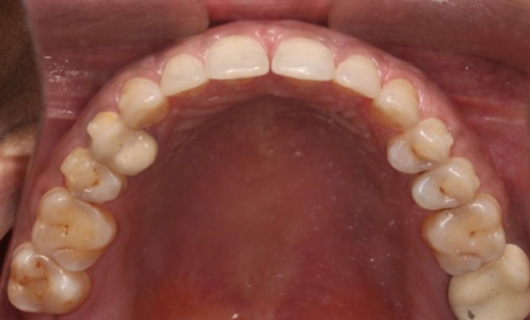

Like braces, Invisalign Braces straighten teeth by placing trays of special material over the teeth in their natural position. A gentle and constant force is used to move the teeth into the desired position without having to go through the hassle of metal wires and brackets. Through digital scanning, they are customized for every patient. Over time, they become a part of the body, since they are so snugly fitting. You are free to eat and drink anything since you will be removing all foods before every meal.